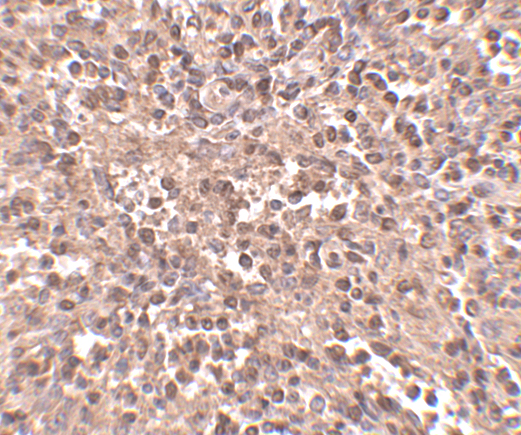

ATG5 antibody can be used for the detection of ATG5 by Western blot at 1 - 2 μg/mL. Antibody can also be used for immunohistochemistry starting at 2.5 μg/mL. For immunofluorescence start at 5 μg/mL.

Antibody validated: Western Blot in rat samples; Immunohistochemistry in human samples and Immunofluorescence in human samples. All other applications and species not yet tested.